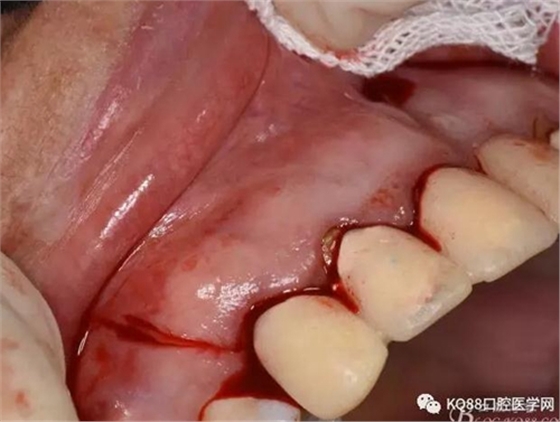

圖7. 分別在13的遠中和11的近中做垂直切口加齦溝內(nèi)水平切口,形成梯形瓣

圖8.翻開梯形瓣